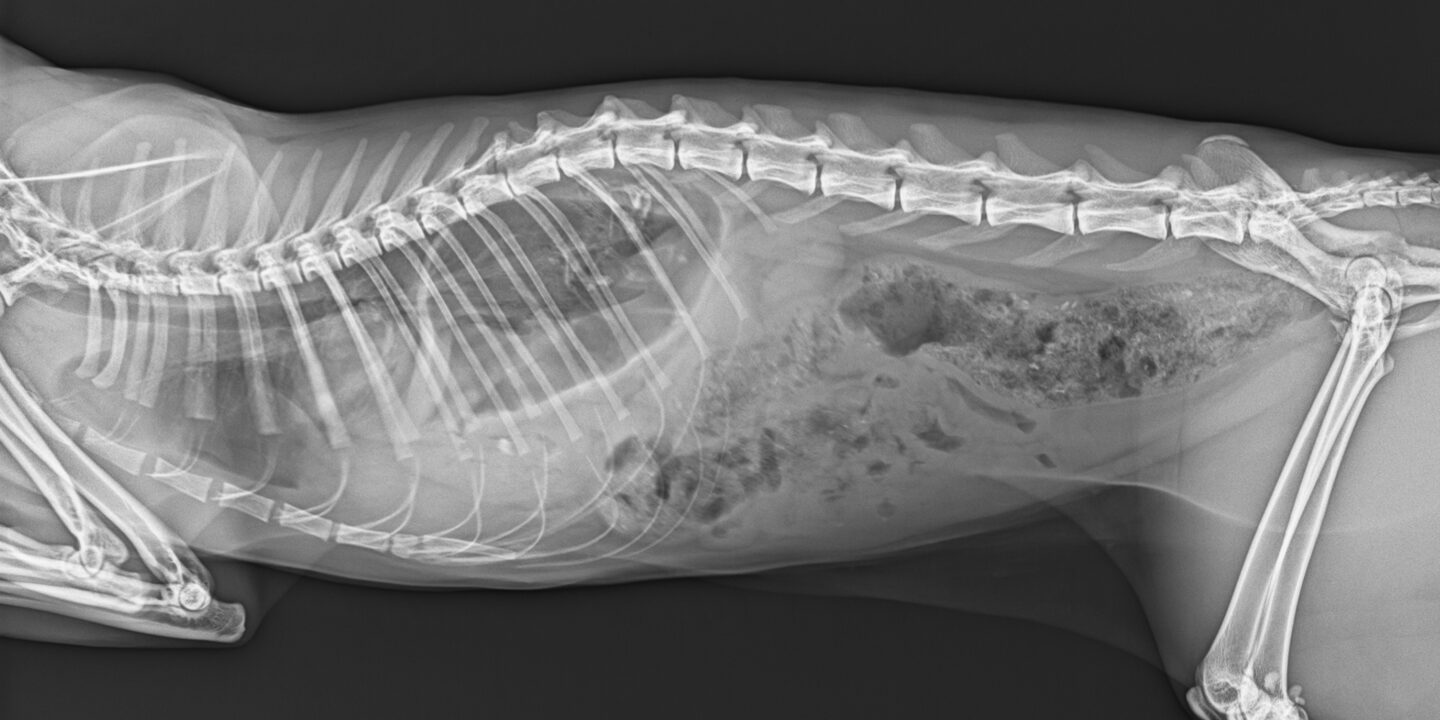

Beckenfrakturen bei Katzen

Wie können wir Beckenfrakturen bei Katzen diagnostizieren, wann soll operativ behandelt werden?

Etwa 25 % aller Frakturen der Katze betreffen das Becken (1), die häufigsten Ursachen sind Autounfälle und Stürze aus großen Höhen bzw. Fensterstürze, wobei die genaue Ursache bei Freigängern oft nur vermutet werden kann.